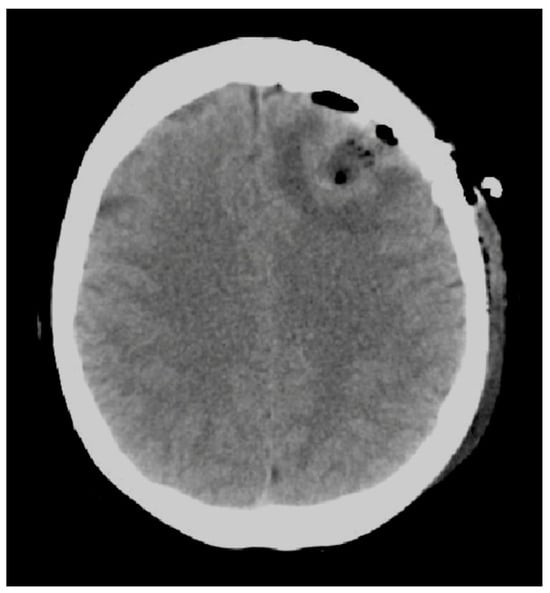

The dural opening was performed in order to show our target and cottonoids were used to protect the healthy cortex and avoid the epidural bleeding. After the identification of the tumor with the neuronavigation passive probe, the tumor resection started with a subpial disconnection technique leaving a thin shell of white matter around the lesion in order to reduce the spread of tumoral cells. The bipolar was used only as a tool to help the dissection maneuvers. Blunt and cold dissection with suction was used in order to avoid vascular and axonal thermic injuries. Moreover, we suggest the use, when needed, of low amperage bipolar coagulation to preserve normal anatomy and the cleavage plane which can be lost by the emulsification of the tissue induced by higher amperages. Furthermore, the gentle use of suction gives an important tactile feedback helping the surgeon to better identify the interface between the tumor and heathy tissue. In addition, the en-bloc resection by avoiding the progressive decompression via piecemeal debulking, reduces the brain shift effect and improves neuronavigation accuracy []. In this case, surgery via an en-bloc approach was obtained with minimal bleeds and without additional neurological deficit. The postoperative CT scan confirmed a complete resection of the tumor without complications (Figure 4) (see the Video S1).

Figure 4.

Shows a postoperative CT scan confirming the absence of surgical complications.